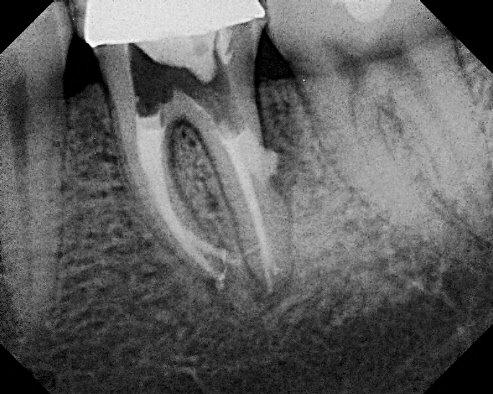

Pour obturer les canaux, il faut les aléser, c’est à dire les élargir et régulariser leur paroi interne. On utilise pour cela des instruments rotatifs proches des forets . Si un canal est coudé, il arrive que l’instrument ne suive pas la coudure et continue à forer dans une mauvaise direction. Ceci s’appelle une fausse route et aboutit à la création d’un faux canal.

Parfois, c’est lors du forage d’un logement pour pivot que la fausse route se produit.

Le diagnostic est facile à faire: les perforations saignent énormément et il faut systématiquement y penser devant une hémorragie endopulpaire. La radio avec des sondes radio opaques en place confirme généralement la perforation.